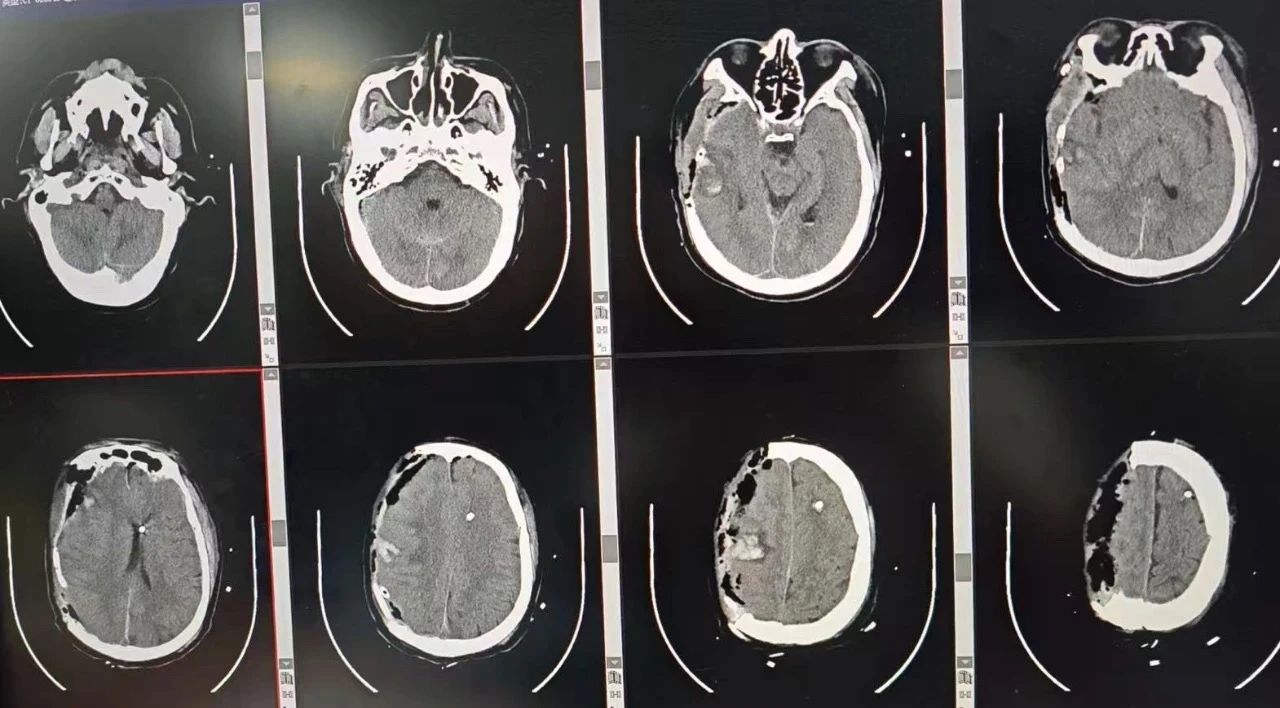

面对脑疝危象,神经外科团队火速投入战斗。李松年主任作技术指导,池超超副主任主刀,实施“开颅脑内血肿清除术+硬膜下血肿清除术+去骨瓣减压术”等联合手术。术中发现患者颅内压高达40mmHg,硬膜下血肿量约100mL,脑组织严重挫裂。团队精准清除血肿、修复受损脑膜,并置入颅内压传感器实时监测。经过不到3小时的鏖战,患者颅内压逐步降至正常范围,手术宣告成功。

神经外科实施实施“开颅脑内血肿清除术+硬膜下血肿清除术+去骨瓣减压术”等联合手术